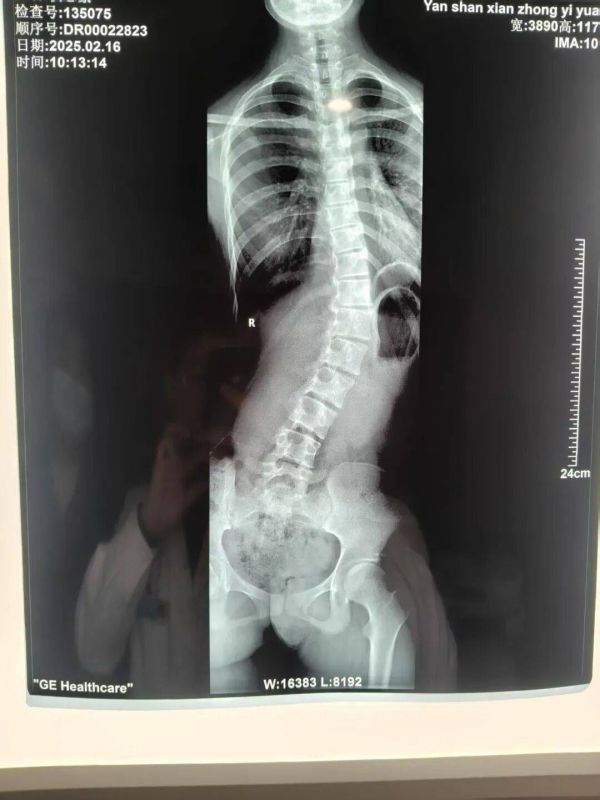

作為孩子生長(zhǎng)發(fā)育的“隱形殺手”,脊柱側(cè)彎不僅影響體態(tài)美觀和身高發(fā)育,嚴(yán)重時(shí)還可能壓迫心肺、引發(fā)疼痛,甚至造成心理自卑。寒假即將到來(lái),正是干預(yù)矯正的黃金期!硯山縣婦幼保健院中醫(yī)科“青少年特發(fā)性脊柱側(cè)彎康復(fù)訓(xùn)練寒假班”正式招募,用專(zhuān)業(yè)中醫(yī)力量,為孩子的脊梁撐起“保護(hù)傘”!

我院中醫(yī)科深耕青少年脊柱健康多年,依托深厚中醫(yī)底蘊(yùn)+現(xiàn)代康復(fù)理念,打造“評(píng)估-矯正-鞏固”全周期管理體系,尤其針對(duì)輕度(Cobb角10°-20°)、中度(20°-40°)側(cè)彎及體態(tài)異常兒童,提供個(gè)性化方案,避免盲目手術(shù)!

1、免費(fèi)初篩評(píng)估:報(bào)名即享專(zhuān)業(yè)脊柱全長(zhǎng)X光分析+Cobb角測(cè)量+體態(tài)評(píng)估,精準(zhǔn)判斷側(cè)彎程度(不含X光等檢查費(fèi));